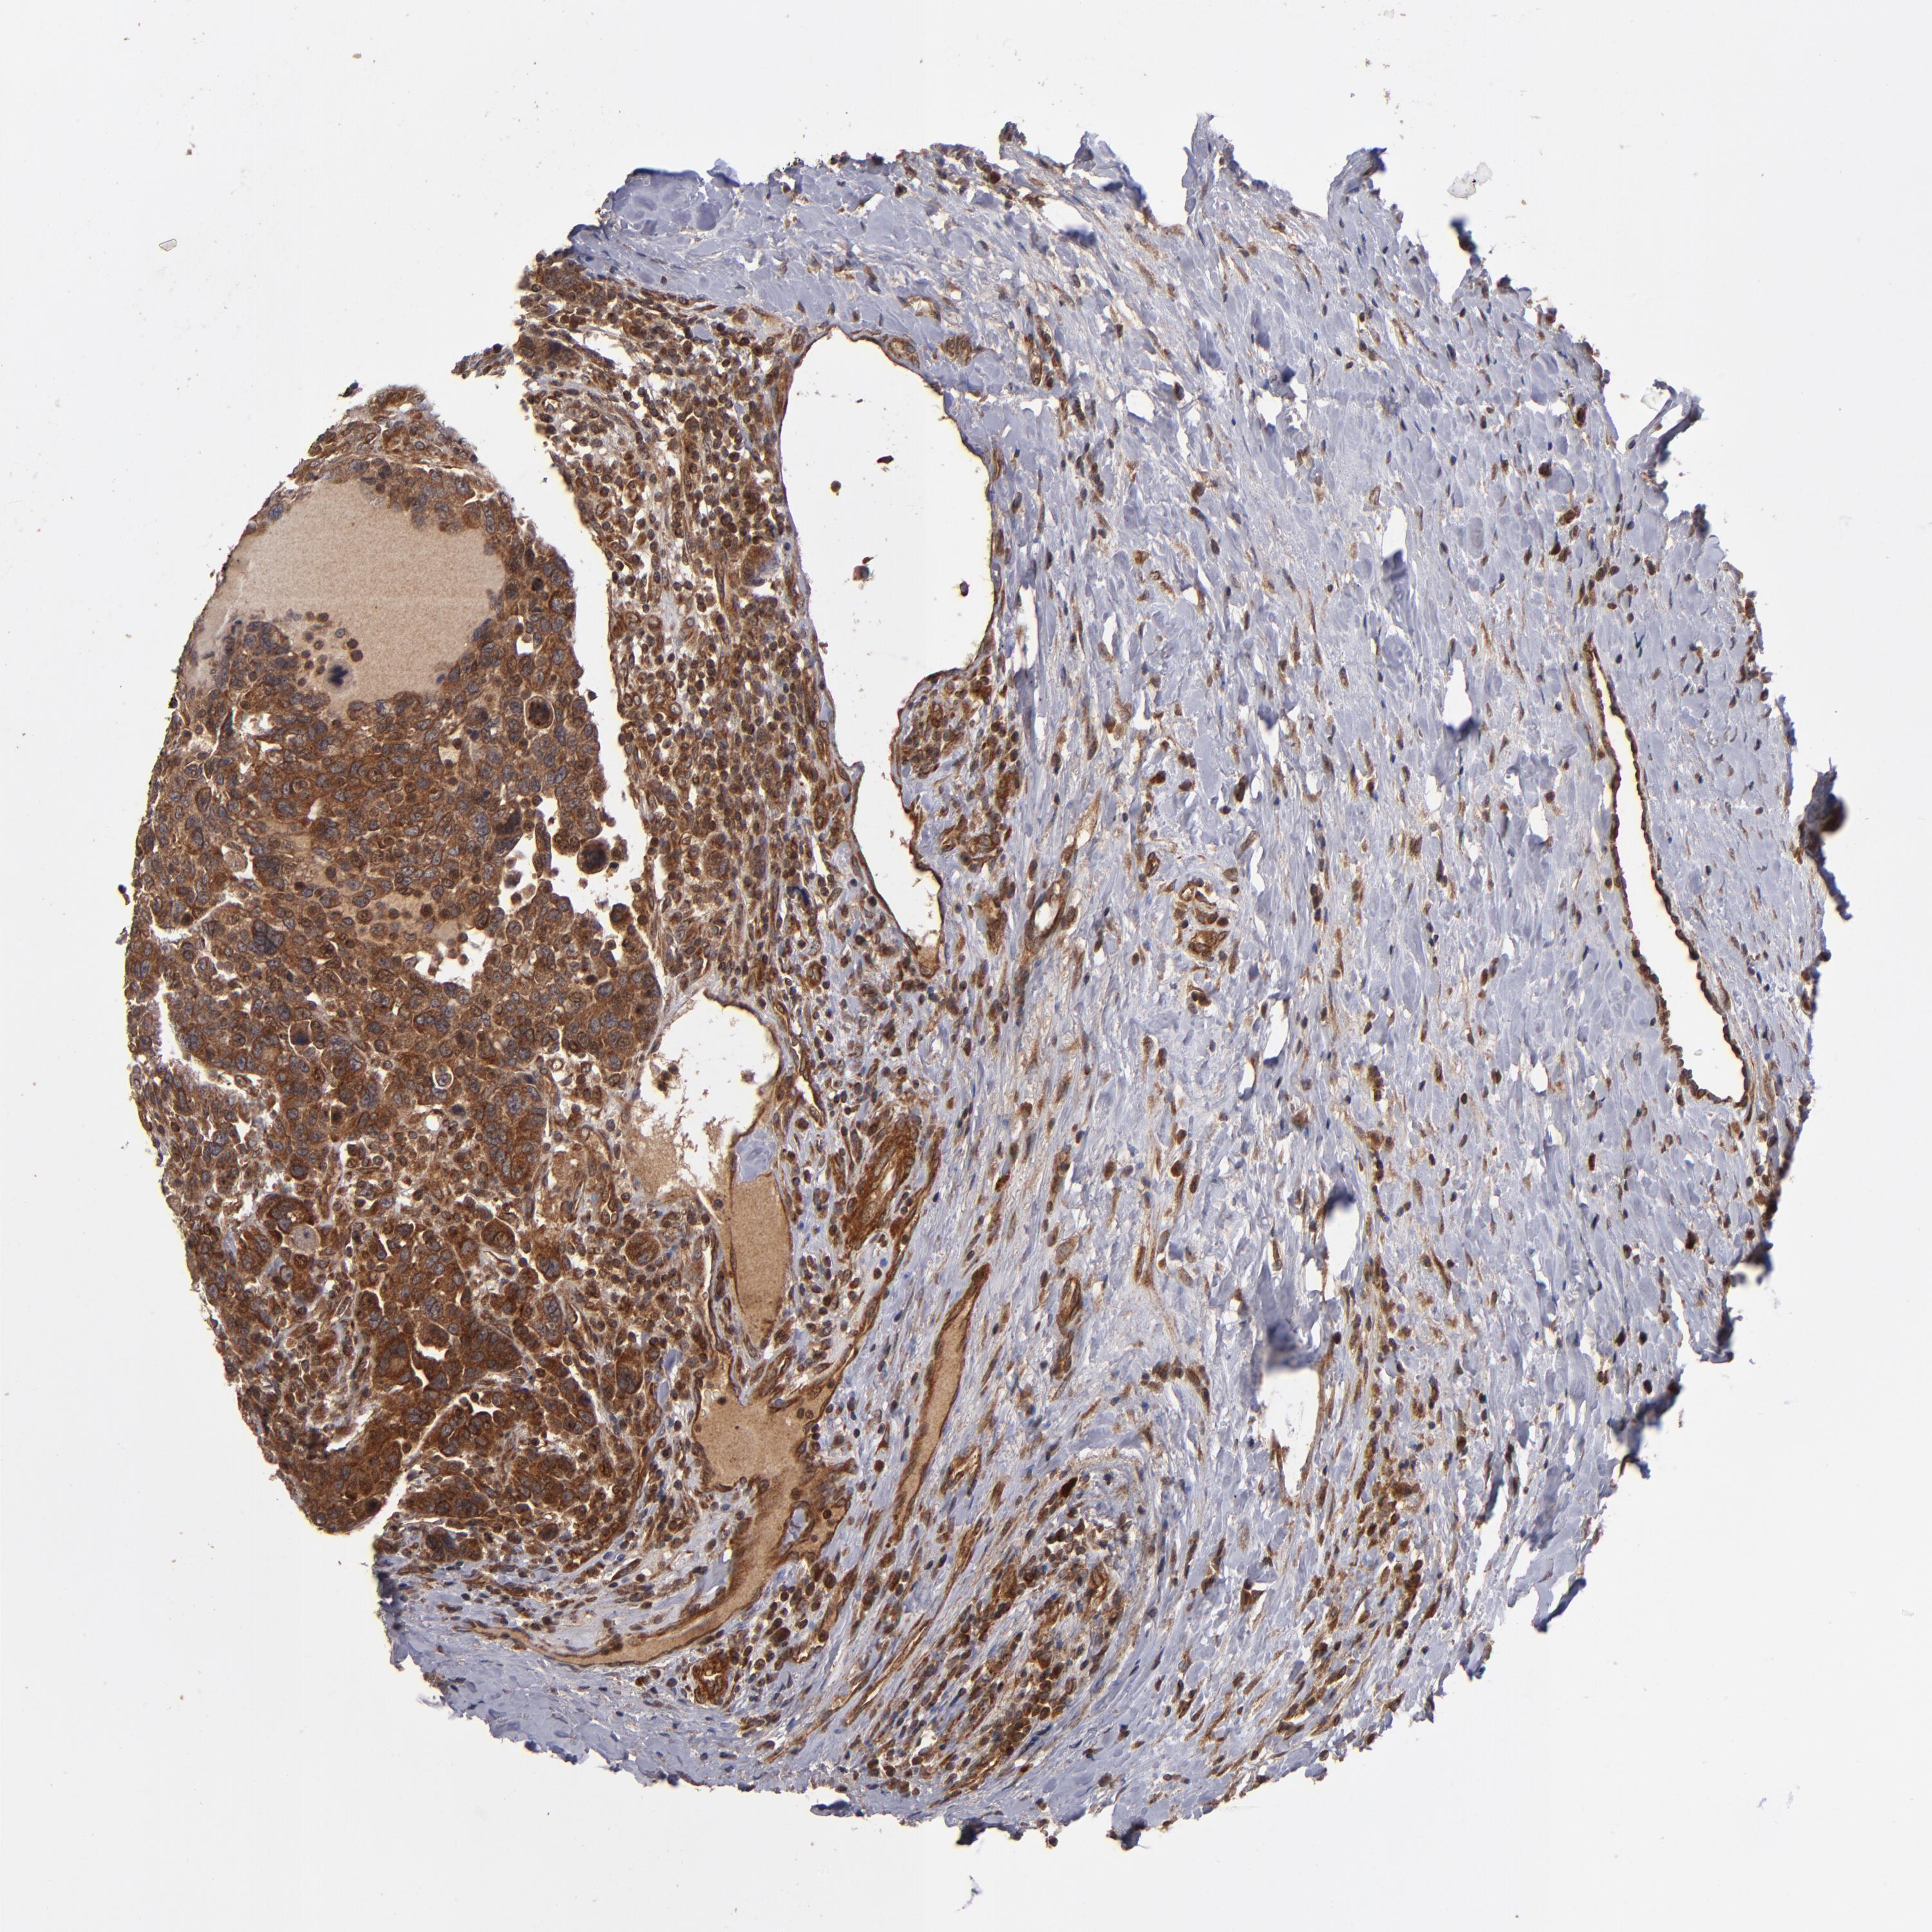

CANCER BREAST CANCER Show tissue menu

BRCA TCGA BRCA VALIDATION PROTEIN EXPRESSION

ANTIBODIES

AND

VALIDATION